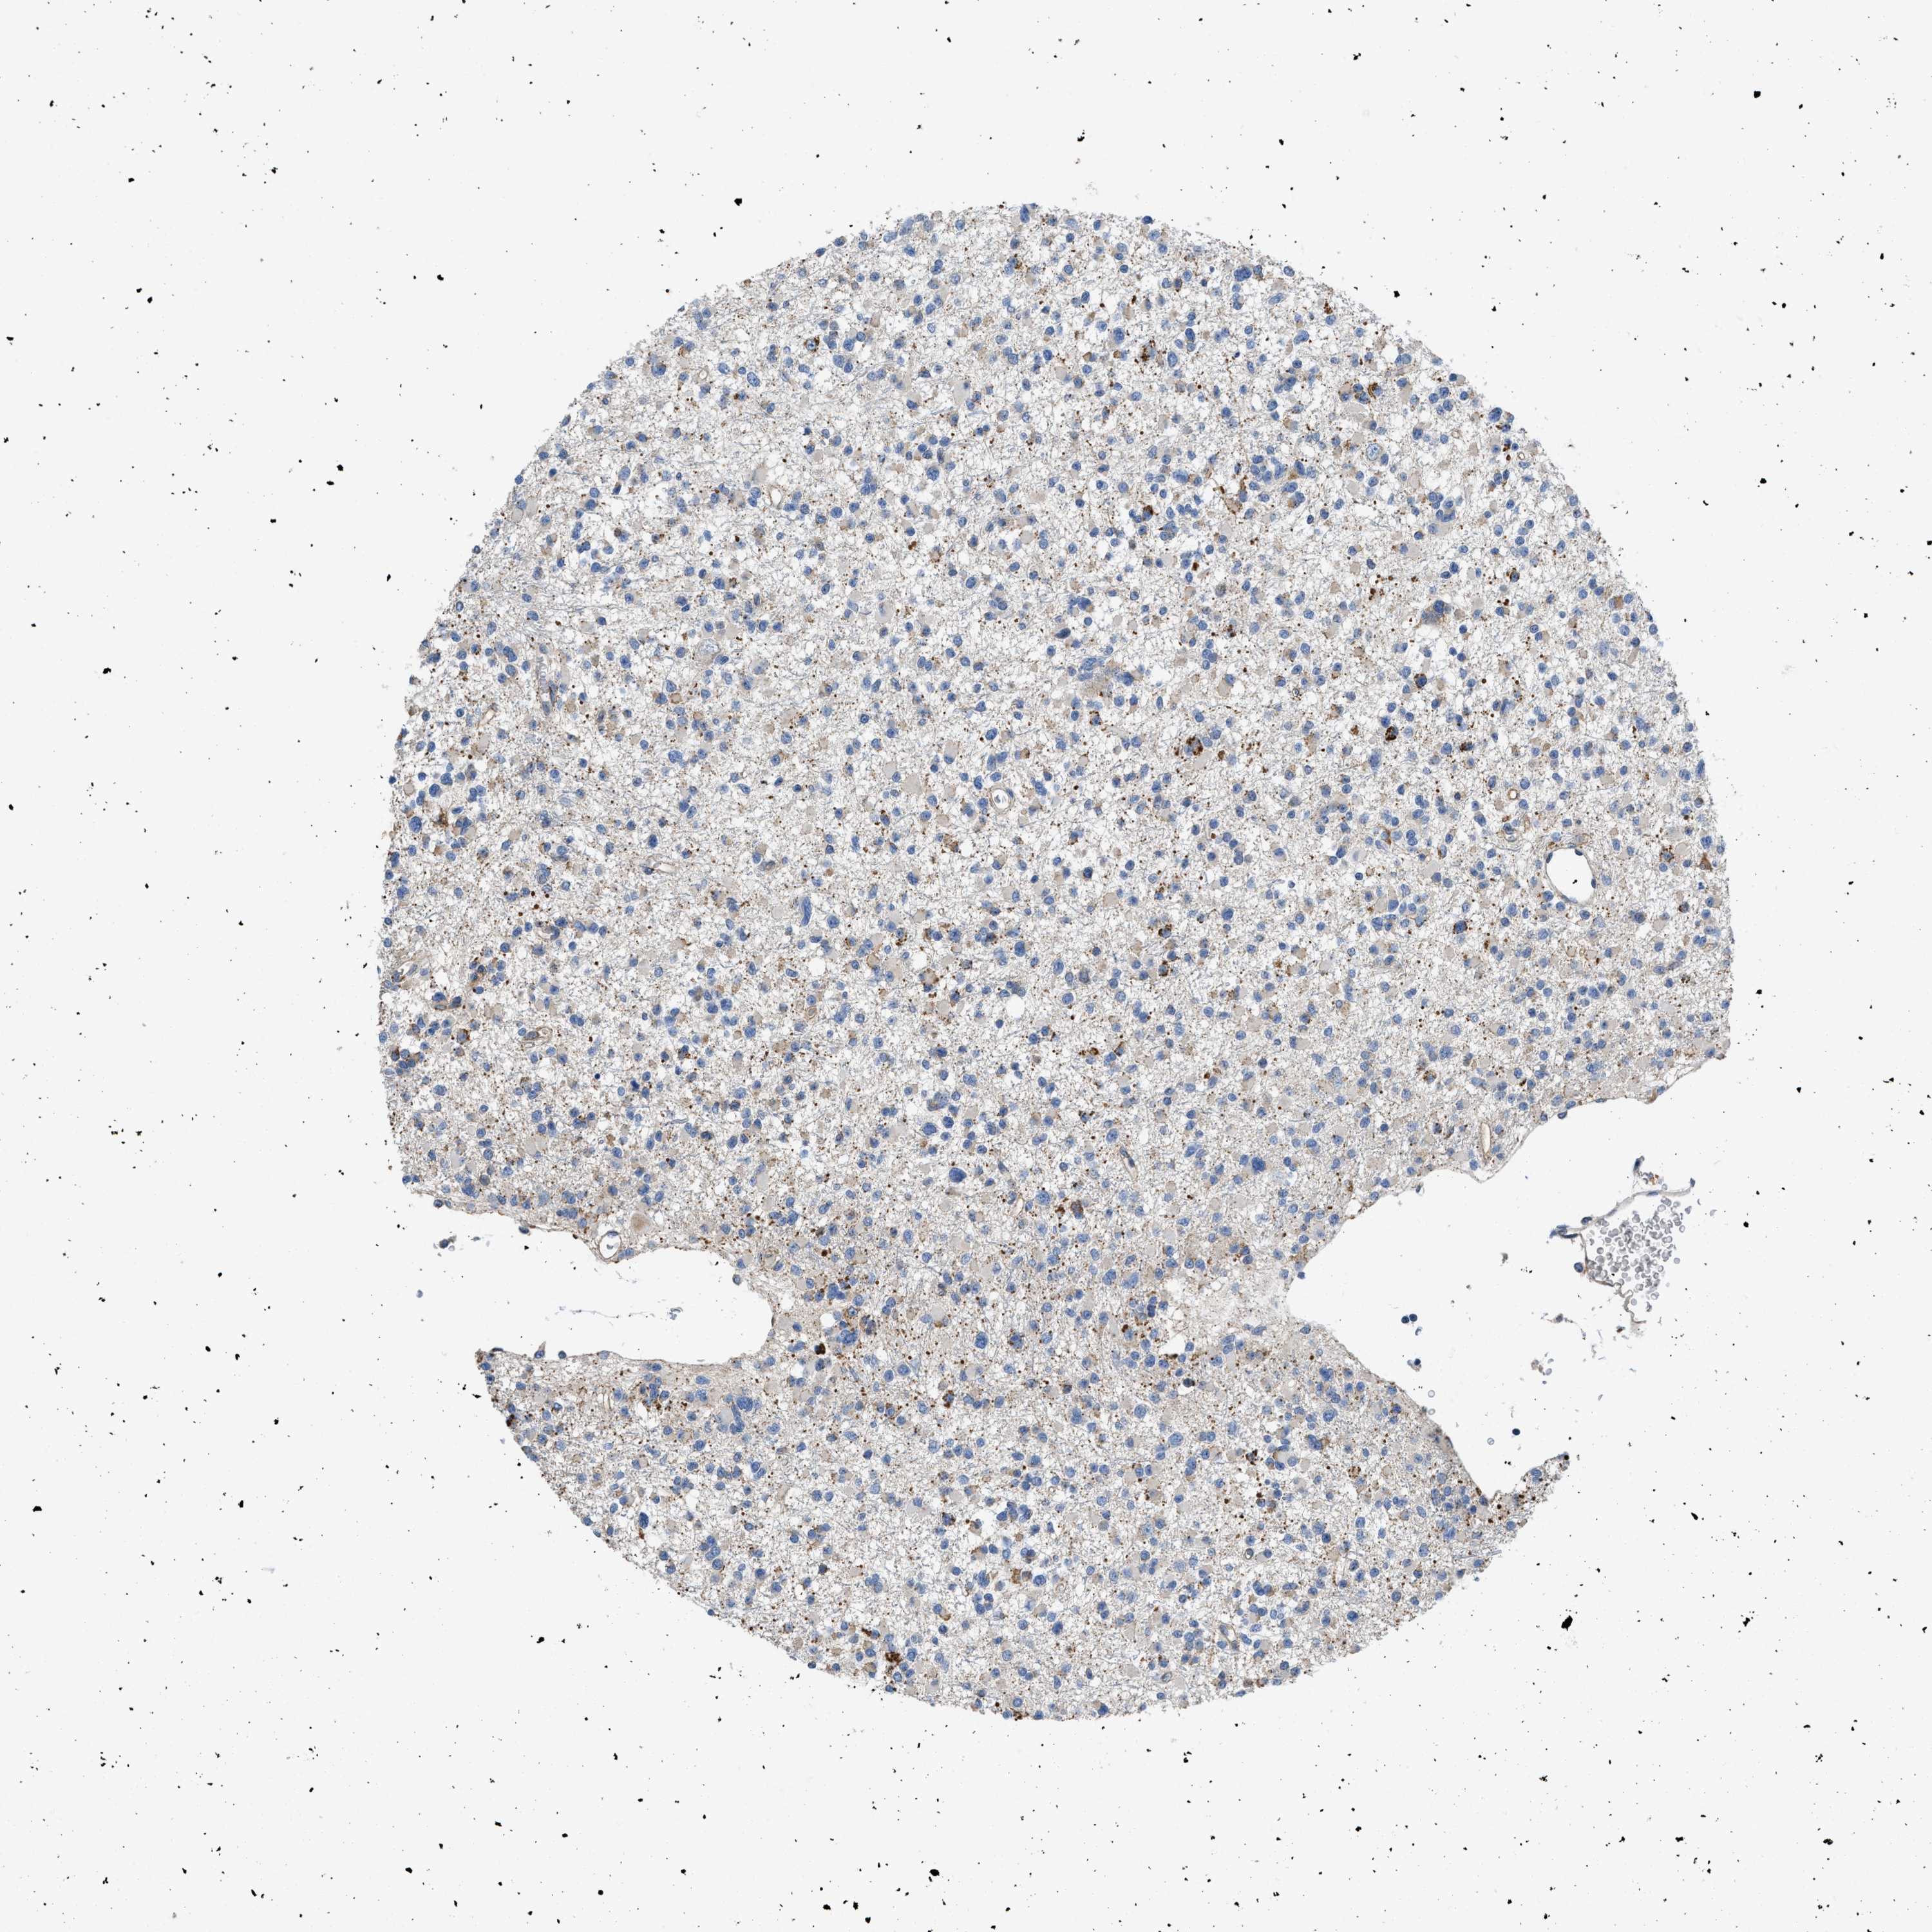

GLIOMA - Protein expressioni

A mouse-over function shows sample information and annotation data. Click on an image to view it in a full screen mode. Samples can be filtered based on level of antibody staining by selecting one or several of the following categories: high, medium, low and not detected. The assay and annotation is described here.

Note that samples used for immunohistochemistry by the Human Protein Atlas do not correspond to samples in the TCGA dataset.

Antibody stainingi

Antibody staining in the annotated cell types in the current human tissue is reported as not detected, low, medium, or high, based on conventional immunohistochemistry profiling in selected tissues. This score is based on the combination of the staining intensity and fraction of stained cells.

Each image is clickable and will lead to virtual microscopy that enables deeper exploration of all samples and also displays staining intensity scores, fraction scores and subcellular localization as well as patient and tissue information for each sample.

Antibody HPA018284

Staining

High

Medium

Low

Not detected

Intensity

Strong

Moderate

Weak

Negative

Quantity

>75%

75%-25%

<25%

None

Location

Nuclear

Cytoplasmic/membranous

Cytoplasmic/membranous,nuclear

Glioma, malignant, High grade

Glioma, malignant, Low grade